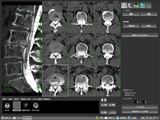

(株)AZEは,Virtual Placeシリーズのオプションとして,新ソフトウエア「疑似超音波(CTUS)」と「マルチアングル・マルチスライス」の2種を発売した。「疑似超音波」は,CT画像を再構成することで,擬似的に超音波画像をつくるソフト。通常の超音波画像よりも空間分解能に優れ,空気の影響を受けないため細部まで認識しやすい画像が得られる。位置関係の把握が容易で,教育用としての実用性も期待できる。一方の「マルチアングル・マルチスライス」は,曲がった腰椎など角度を認識して,自動的に直交断面を探して平面画像として表示。椎体のCT検査での画像処理時間の削減を実現する。